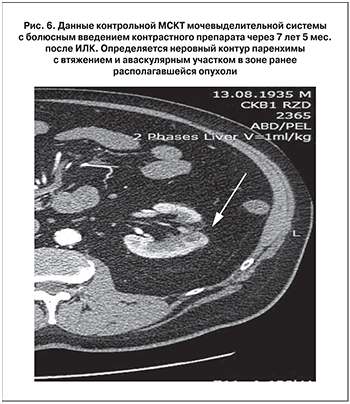

В течение 8,5 лет каждые 12 мес. проводится контрольная МСКТ мочевыделительной системы с болюсным контрастированием (рис. 6). Мониторинг на предмет выявления рака предстательной железы осуществляется на основании данных ТРУЗИ (рис. 7).

За период наблюдения признаков рецидива опухоли почки, а также опухоли предстательной железы не выявлено. Антиандрогенная терапия не проводится, уровень ПСА от 15.10.2018 0,3 нг/мл.